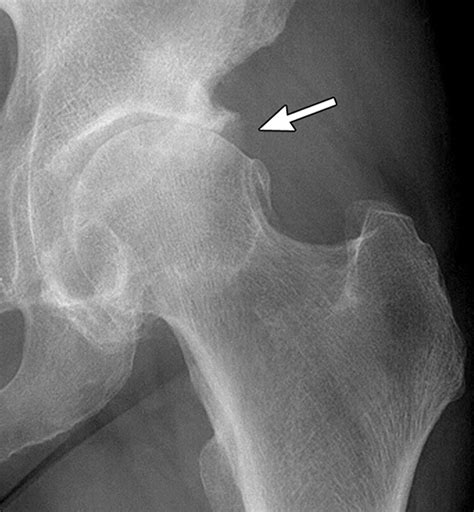

Diagnosing Hip Bone Spurs

Diagnosing a hip bone spur typically involves a combination of medical history, physical examination, and imaging tests. Here are the steps involved in the diagnostic process:

• Imaging Tests: Various imaging tests can help confirm the presence of a hip bone spur. These may include:

Imaging Test Description

X-ray Provides clear images of bones and can detect the presence of bone spurs.

These imaging tests are crucial for determining the exact location and size of the hip bone spur, as well as any underlying conditions that may be contributing to its development.